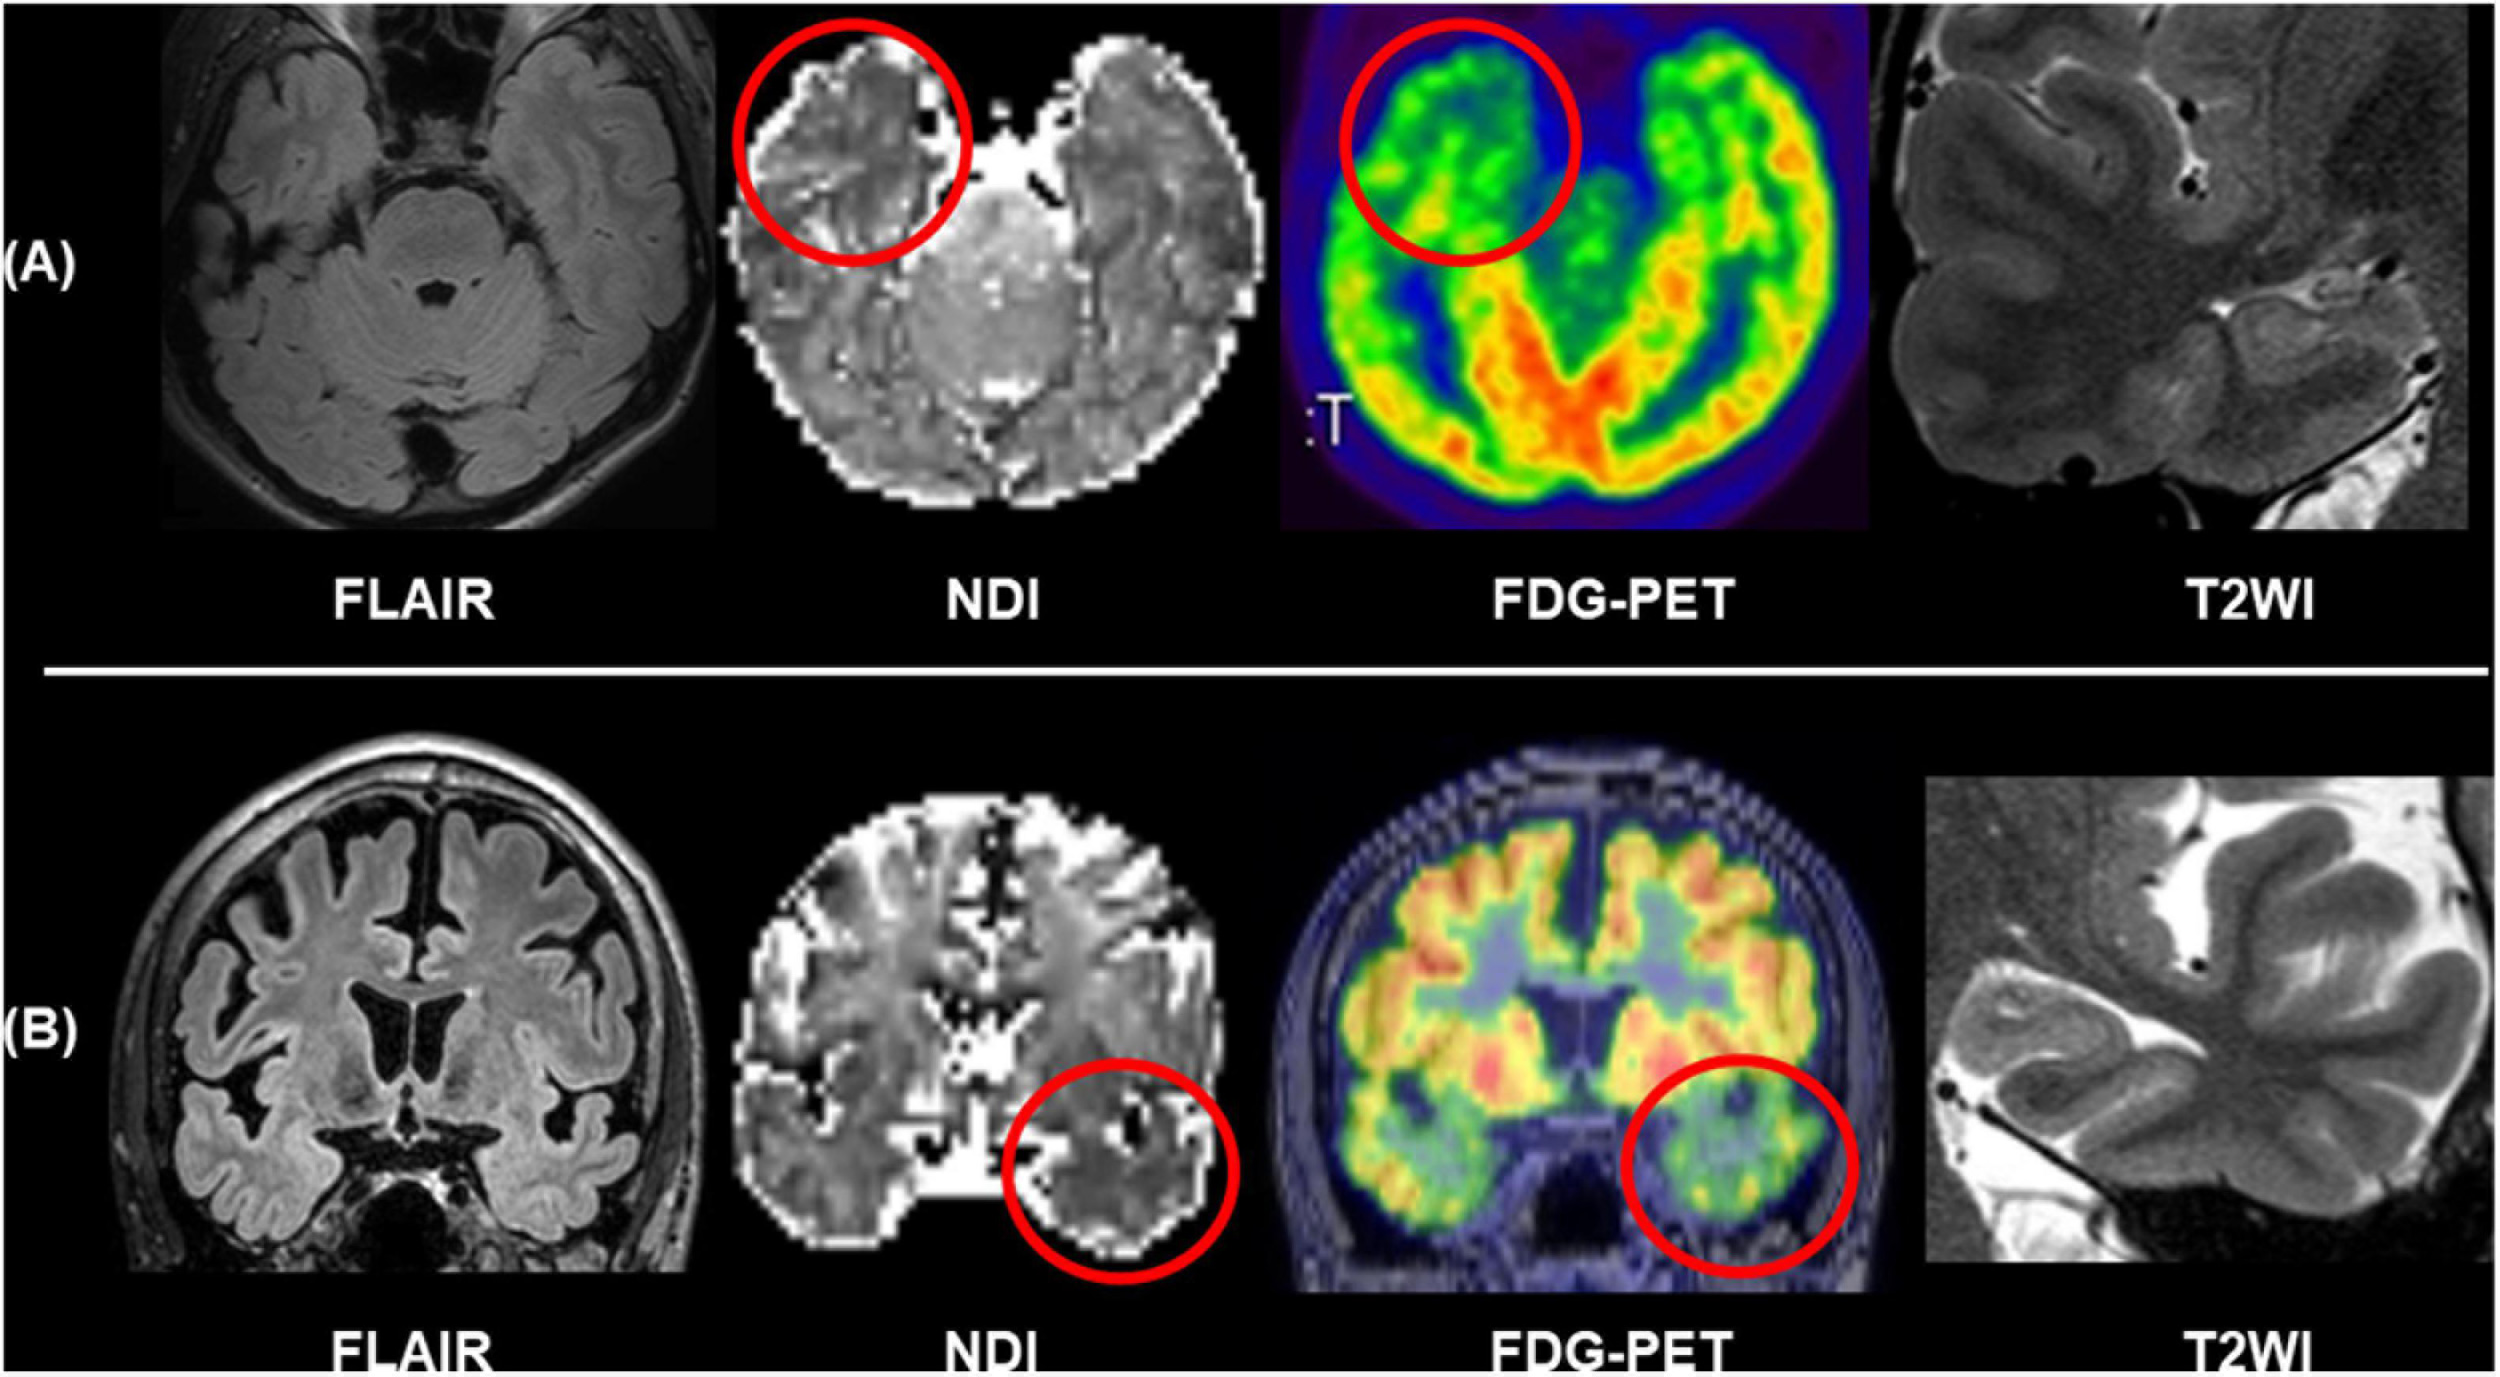

The progress in diffusion MRI has been an emerging topic in the field of neurology and psychiatry. Particularly, multi-shell protocols of diffusion MRI, including diffusion kurtosis imaging (DKI), q-space imaging (QSI), restriction spectrum imaging (RSI), and neurite orientation dispersion and density imaging (NODDI), have provided further information on brain microstructures (Cohen and Assaf, 2002; Jensen et al., 2005; White et al., 2013; Sone, 2019). In the field of epilepsy, NODDI and RSI have been repeatedly reported for their usefulness (Winston et al., 2014; Loi et al., 2016; Reyes et al., 2018; Rostampour et al., 2018; Sone et al., 2018; Lorio et al., 2020; Winston et al., 2020; Shao et al., 2021). Neurite orientation dispersion and density imaging allows us to investigate neurite density and orientation dispersion of the brain microstructures, and reduced neurite density has been consistently found in visible focal cortical dysplasia (Winston et al., 2014; Lorio et al., 2020). Neurite orientation dispersion and density imaging may also visualize neurite abnormalities within the focus even in MRI-negative cases (Sone et al., 2018). Figure 6 represents two cases with conventionally MRI-negative PET-positive unilateral TLE, which showed reduced neurite density within the anterior temporal lobe of the focus side. In TLE with hippocampal sclerosis, reductions of neurite orientation dispersion as well as neurite density were reported (Sone et al., 2018). Additionally, NODDI could help in better visualization of cortical tubers in tuberous sclerosis (Shao et al., 2021). RSI is another advanced diffusion MRI using multi-shell, reduced neurite density, and its correlation with clinical symptoms in epilepsy was also confirmed by RSI (Loi et al., 2016; Reyes et al., 2018). Thus, advances in diffusion MRI may be a promising tool for patients with drug-resistant focal epilepsy and invisible lesions on conventional MRI.

FIGURE 6

Two cases of conventionally MRI-negative PET-positive TLE. While no abnormalities were found in FLAIR and T2WI including the hippocampus, neurite orientation dispersion and density imaging (NODDI) revealed reduced neurite density of the focus side. (A) Modified from Sone et al. (2018). (B) Modified from Sone (2019).